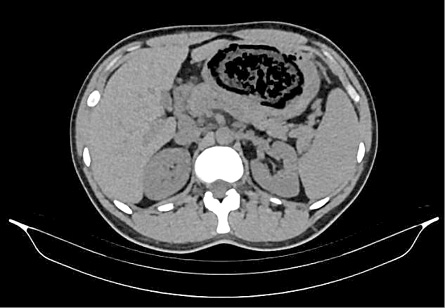

A thirty two years old male patient presented to our surgery department with complain of postprandial abdominal pain, early satiety and occasional vomiting episodes. He lost 5–6 kg in the past 6 months. The symptoms were present for the last 1 year. No comorbidity was reported. Previously he underwent a gastroscopy in another hospital where a stomach bezoar and large ulcer was diagnosed (Figure 1). Plain x-ray (Figure 2), computerized tomography (CT) scan (Figures 3 and 4) and gastroscopy were conducted in our institution. The gastroscopic examination reported giant rough bezoar impossible for endoscopic retrieval.

Figure 3. Axial computerized tomography scan with visual bezoar